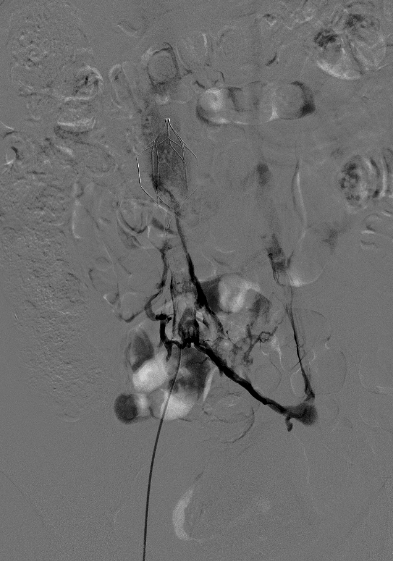

术中造影发现下腔静脉滤器内+下腔静脉+右髂总静脉陈旧性血栓机化闭塞,合并髂外静脉及股静脉近段亚急性血栓

血栓被逐步清除,右髂静脉和下腔静脉闭塞段一点点被开通,整整 3 个小时,徐勋华主任带领团队保持着高度的专注和精细的操作。

「通了!血流恢复了!」当下腔静脉最后闭塞段成功开通,造影显示血流通畅时,导管室内所有人都松了一口气。